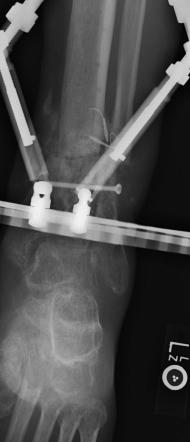

Postoperative (13th) images of left ankle

The image(s) displayed here were created following Liam's 13th surgery which was performed by Dr. Saunders. After a few hiccups getting

the surgery scheduled, Liam spent most of the September 13th afternoon in his 13th surgery. ;-) The surgery lasted about 5 hours and according

to the doctor, it was a good surgery. The 1st photo shows the new frame bracing that holds Liam's ankle together. The next series of photos show

various angles of the ankle and the rods that go from the frame into and through the left ankle. There was some concern that the swelling would

burst and allow for infection. Looks like we are now past that concern. Liam is still on antibiotics to ward of potential infection. The flesh

images show how the skin reacts to having the leg adjusted by the brace. The doctor has had to cut the skin to allow the rods to move freely.